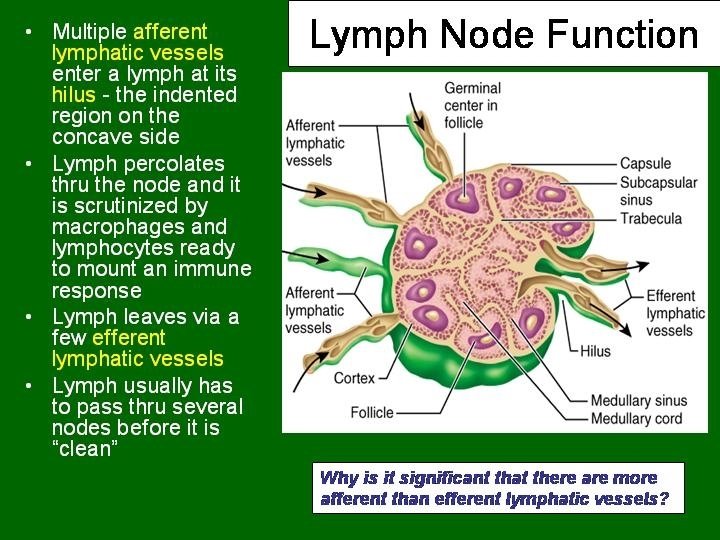

Lymph Node • • • Capsulated Afferent lymphatics “subcapsular sinus” Hilum – blood vessels, efferent lymphatic Cortex and medulla Cortex – Lymphatic nodules, germinal centres – “Paracortex” T-dependent zone • Medulla – Medullary cords and sinusoids M C

LYMPH NODES These are the smallest but most numerous encapsulated lymphoid organs. Scattered in groups along lymphatic vessels , they act as in-line filters of the lymph, removing antigens and cellular debris and adding Igs. Lymph nodes are bean-shaped structures with convex and concave surfaces. The parenchyma consists of a peripheral cortex, adjacent to the convex surface, and a central medulla lying near the depression (hilum) in the concave surface. The connective tissue capsule gives off trabeculae that penetrate between the cortical nodules and subdivide the cortex. Cortex. The cortex is dark-staining owing to the presence of tightly packed lymphocytes. These are suspended in a reticular connective tissue network and arranged as a layer of typical secondary lymphoid nodules (containing primarily B lymphocytes) with germinal centers. The cortex also contains reticular cells, antigen-presenting follicular dendritic cells, macrophages, a few plasma cells, and some helper T cells.

Medulla. Lighter staining than the cortex, the medulla is composed of cords of lymphoid tissue (medullary cords) separated by medullary sinuses. The lymphocytes are mainly small, less numerous than in the cortex. The cords are also rich in reticular cells and fibers and contain many plasma cells that have migrated from the cortex. Paracortical zone. This is the T-dependent region, lying between the cortical lymphoid nodules and the medulla. It contains mainly T lymphocytes suspended in a reticular connective tissue. B lymphocytes, plasma cells, macrophages, and antigen-presenting interdigitating dendritic cells may also be present. Lymphatic vessels. Sinuses (subcapsular, peritrabecular, medullary). Functions: 1. Filtration of lymph 2. Lymphocyte production (lymphopoiesis). 3. Immunoglobulin production.